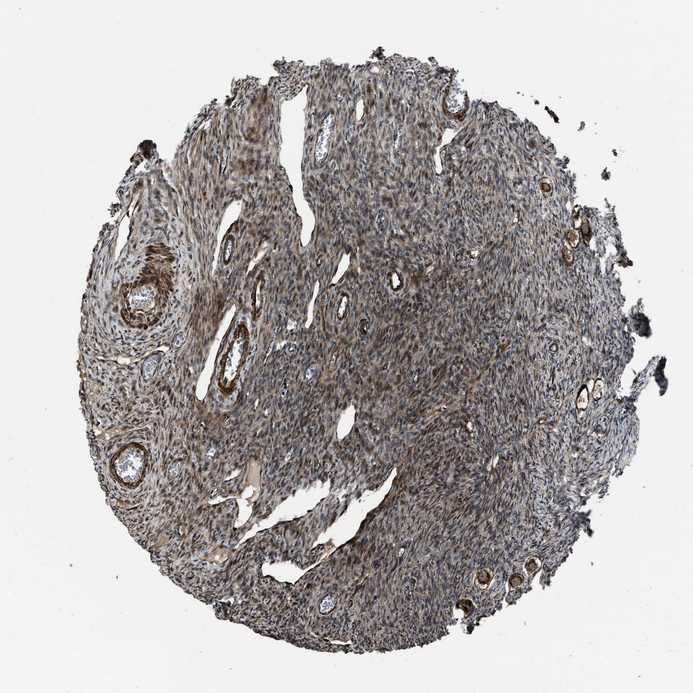

NSD3